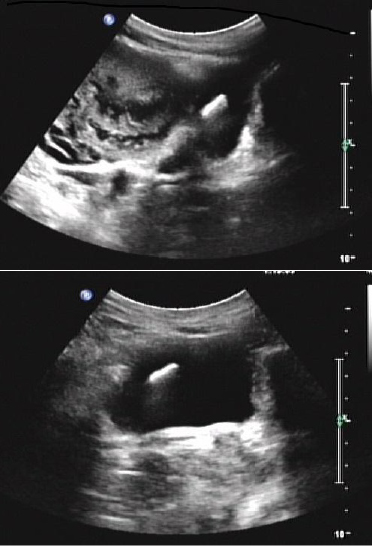

Figure 1: Consistent with an intrauterine device.

figure 1